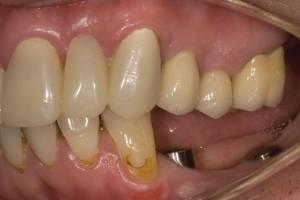

Alternatively, fixed crown and bridgework could be used in jaws with no teeth at all, when rows of teeth that are screwed in place, offering the ultimate aesthetic appearance in function and comfort. The following example is where a simple fixed bridge was constructed on two implants to replace three teeth on the patient’s lower left hand side:

Completed crown and bridgework on implants